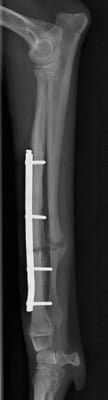

固定強度は右前肢のが強く、跛行の回復も早いはずですが、

このイタグレさんは手術直後から左前肢をより使ってました。

この段階でもしっかり負重し、歩いています。

左前肢を右より先に積極的に負重する事は想定外でした。

もう少し強度を高めておけば、よりこの時点でもより

仮骨形成を認めたと思われます。

治療経過はレントゲンだけで判断できません。

順調に足への負荷が増えていることも大切です。